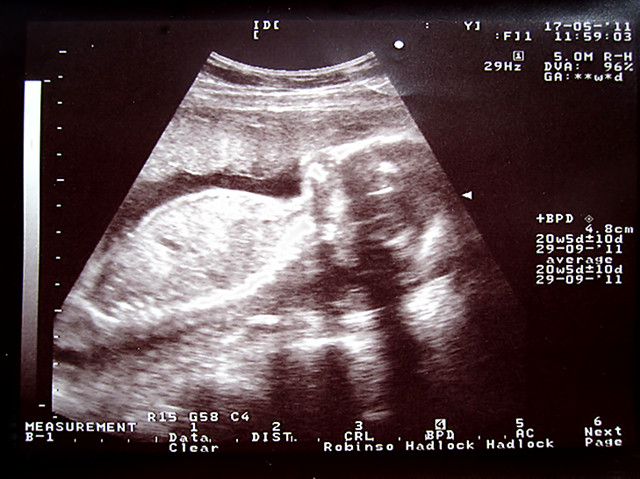

5.17 第五次B超

Sheyla是个大孩子了 头围就有4.8CM了

20周+5天 身高20CM 体重0.5KG